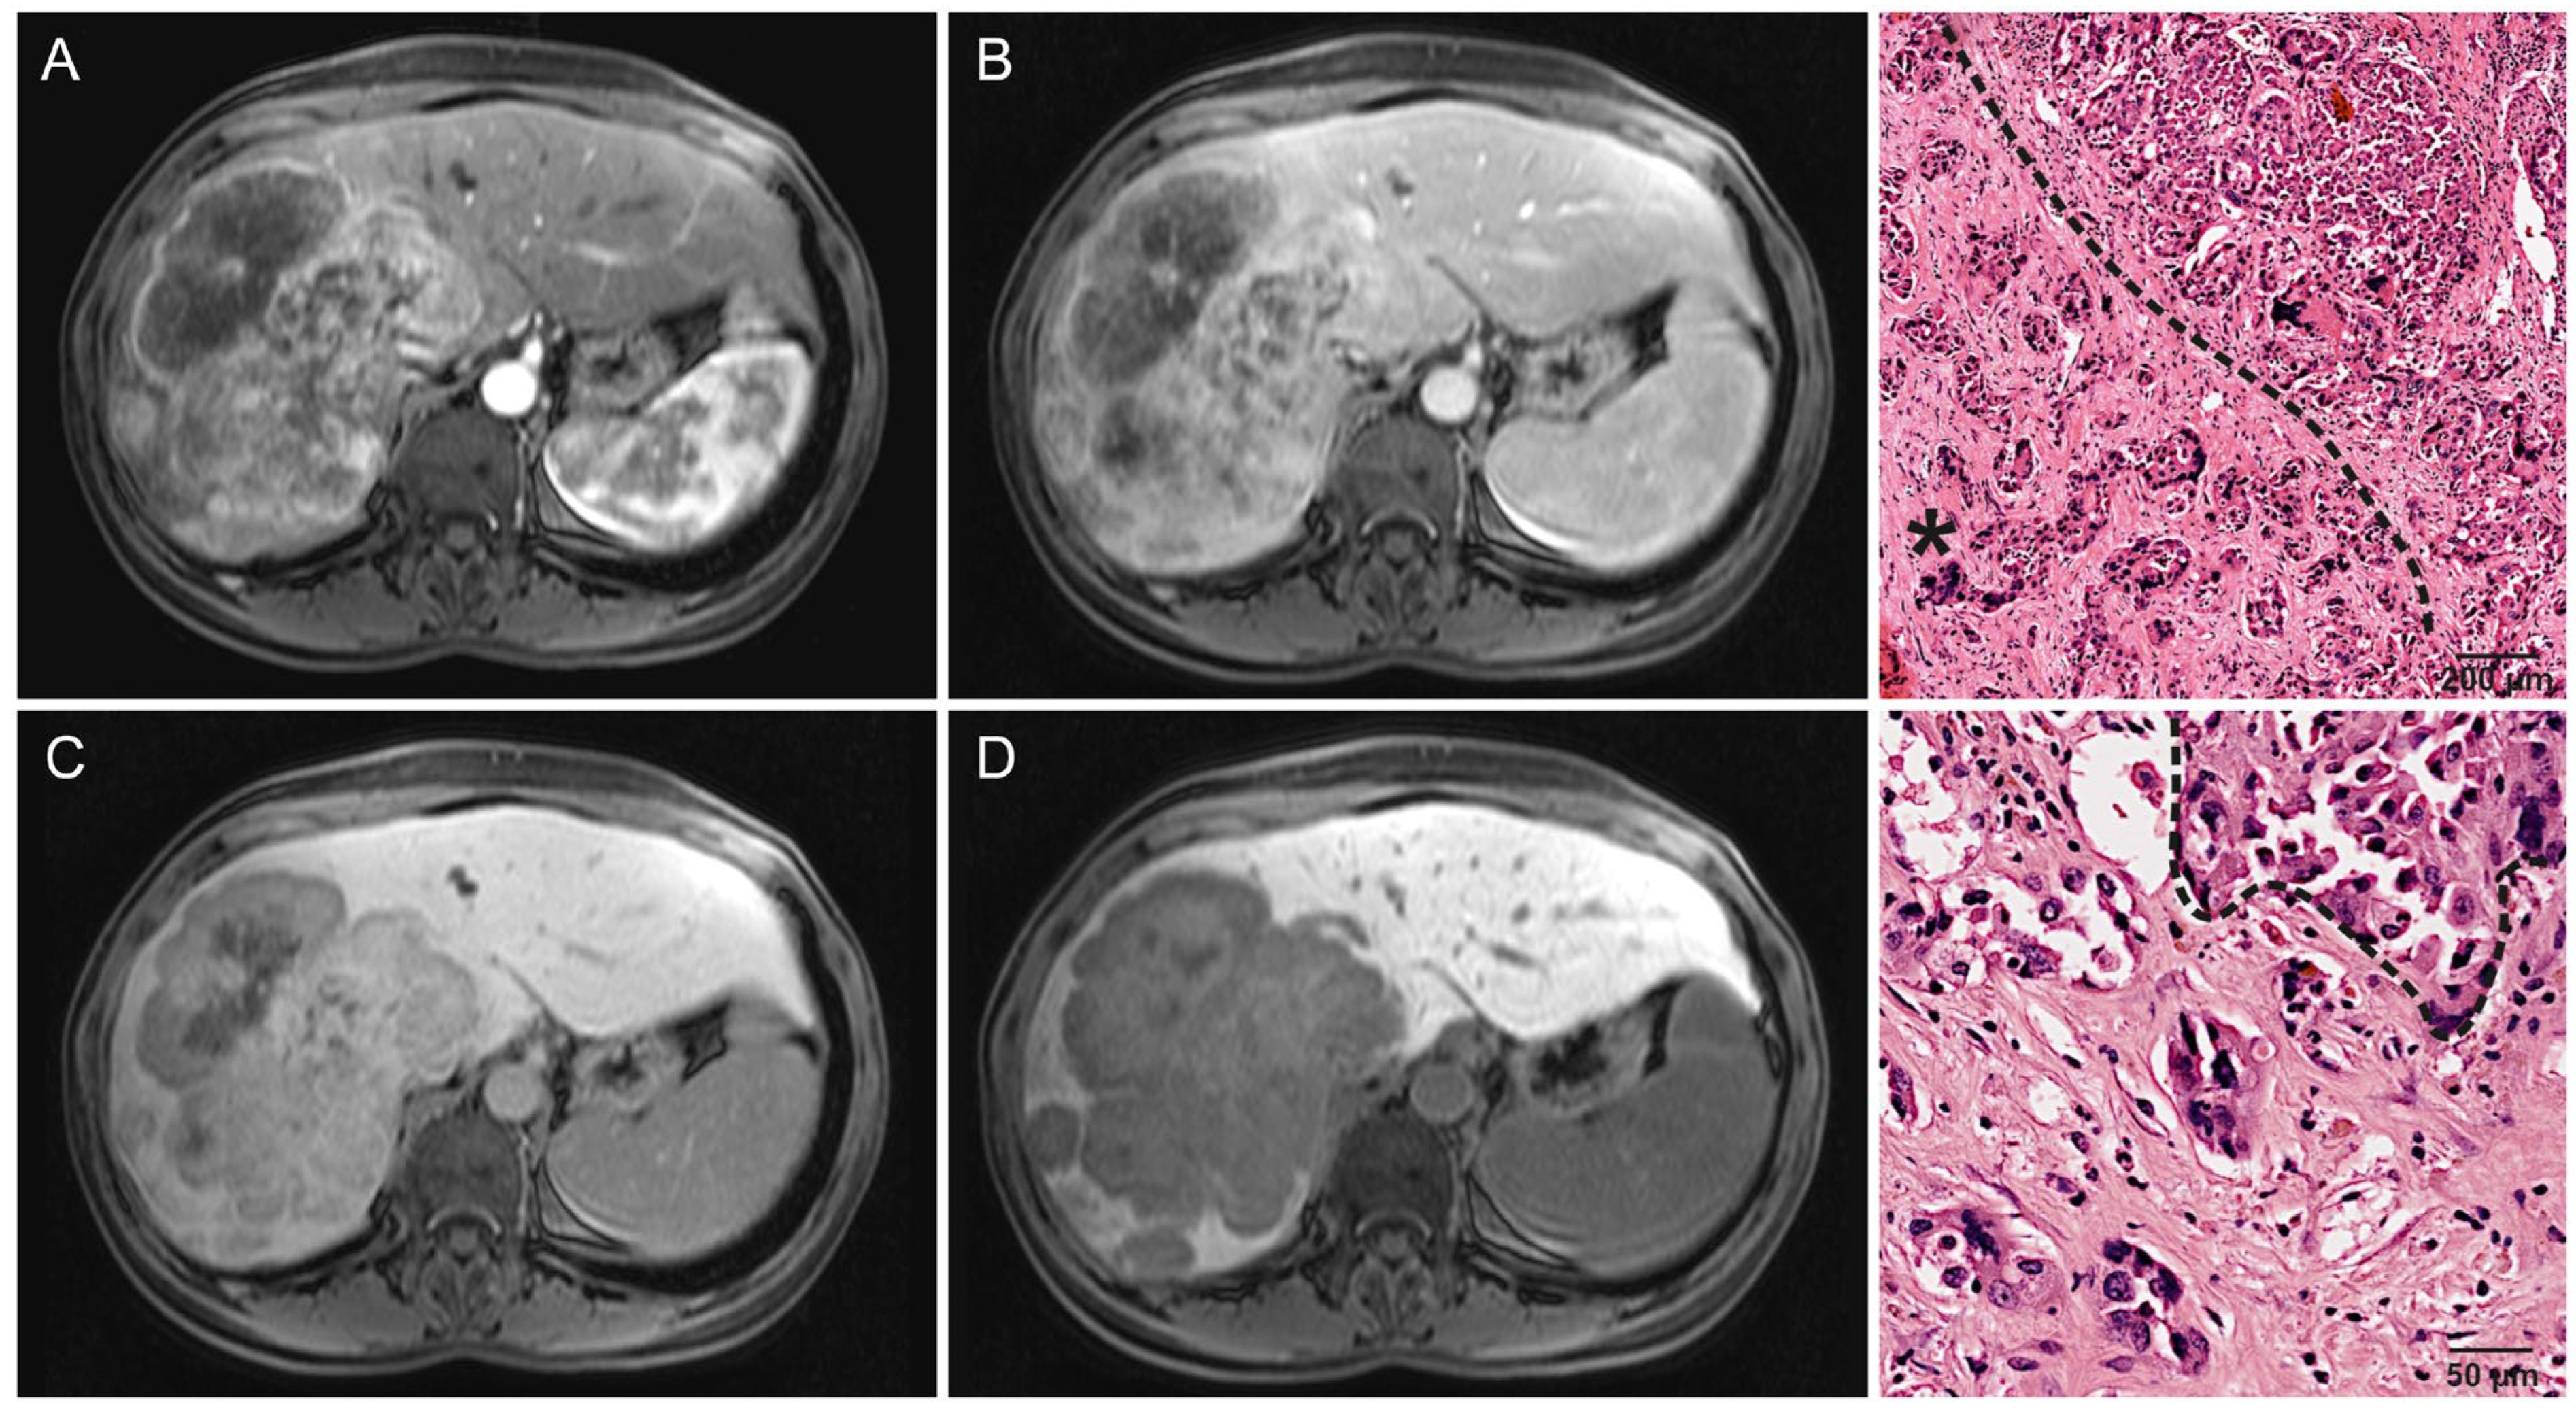

- Kang, Y.; Lee, J.M.; Kim, S.H.; Han, J.K.; Choi, B.I. Intrahepatic mass-forming cholangiocarcinoma: Enhancement patterns on gadoxetic acid-enhanced MR images. Radiology 2012, 264, 751–760. [Google Scholar] [CrossRef] [PubMed]

- Chung, Y.E.; Kim, M.J.; Park, Y.N.; Choi, J.Y.; Pyo, J.Y.; Kim, Y.C.; Cho, H.J.; Kim, K.A.; Choi, S.Y. Varying appearances of cholangiocarcinoma: Radiologic-pathologic correlation. Radiographics 2009, 29, 683–700. [Google Scholar] [CrossRef] [PubMed]

- Min, J.H.; Kim, Y.K.; Choi, S.Y.; Kang, T.W.; Lee, S.J.; Kim, J.M.; Ahn, S.; Cho, H. Intrahepatic Mass-forming Cholangiocarcinoma: Arterial Enhancement Patterns at MRI and Prognosis. Radiology 2019, 290, 691–699. [Google Scholar] [CrossRef] [PubMed]

- Jin, K.P.; Sheng, R.F.; Yang, C.; Zeng, M.S. Combined arterial and delayed enhancement patterns of MRI assist in prognostic prediction for intrahepatic mass-forming cholangiocarcinoma (IMCC). Abdom. Radiol. 2022, 47, 640–650. [Google Scholar] [CrossRef]

| Margin | 0.006 * | ||

| Irregular | 83% (39/47) | 47% (9/19) | |

| Sharp | 17% (8/47) | 53% (10/19) | |

| Growth pattern | 0.005 * | ||

| Infiltrative | 70% (33/47) | 32% (6/19) | |

| Solid | 30% (14/47) | 68% (13/19) | |